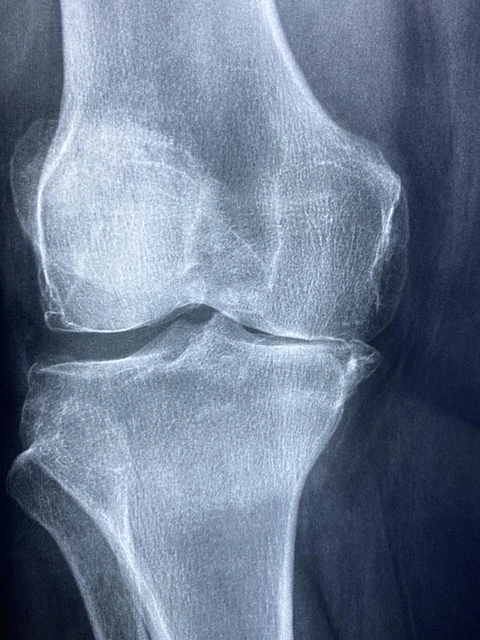

์ค์ ํ๊ธฐ: ์์ ํ ์ด๋ค ๋ณํ๊ฐ ์์์๊น?

๊ธ์ ์ ์ธ ํ๊ธฐ

- “๊ณ๋จ ๋ด๋ ค๊ฐ ๋ ๋๋ฌด ์ํ ๋๋ฐ, ์ง๊ธ์ ํต์ฆ์ด 80% ์ด์ ์ค์์ด์.”

- “์ฌํ์ด๋ ์ด์ฌํ ํ๋๊น ๋ฌด๋ฆ์ด ํจ์ฌ ๋ถ๋๋ฌ์์ก์ด์.”

์์ฌ์ด ํ๊ธฐ

- “์ด๊ธฐ์ ๋ฌด๋ฆฌํด์ ๋ค์ ํต์ฆ์ด ์ฌํด์ก์ด์.”

- “์ฌํ์ ๊ฒ์๋ฆฌํ๋๊น ํจ๊ณผ๊ฐ ์ค๋๊ฐ์ง ์๋๊ตฐ์.”

๊ฒฐ๋ก : ๋ฏธ์ธ์ฒ๊ณต์ ์ ์ฐ๊ณจ ์น๋ฃ์ ์์์ผ ๋ฟ, ์ง์ง ์น๋ฃ๋ ์์ ์ดํ ‘๊ด๋ฆฌ’์ ๋ฌ๋ ค ์์ต๋๋ค.